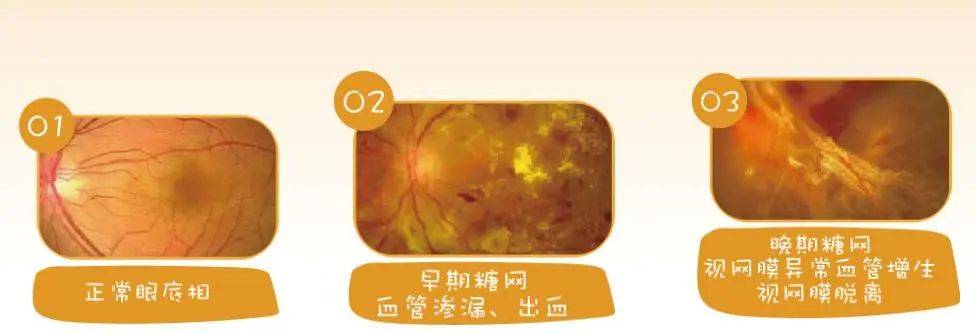

眼科主任主任医师朱冬梅提醒:一旦得了糖尿病,失明概率是正常人的25倍!糖尿病是一种代谢性疾病,看起来似乎与眼睛,没有太大的关系,实际上糖尿病的并发症,可怕到令人发指。糖尿病患者失明的概率是正常人的25倍,是名副其实的"光明杀手"。

有研究统计:中国有近1.3亿的糖尿病患者,这其中约有30%,患有糖尿病视网膜病变,这其中又有超过1000万人面临失明的威胁。可以这样说,几乎所有的眼病,都可能发生在糖尿病患者身上。

比如说视网膜病变、白内障、眼外肌麻痹等,其中,视网膜病变最为常见,晚期可导致玻璃体出血、视网膜脱离而失明。